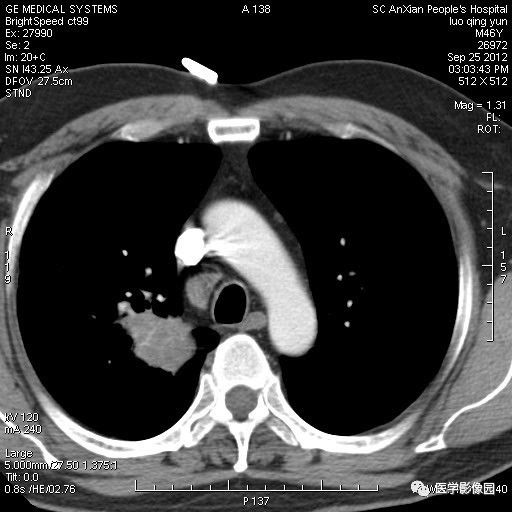

影像学表现:右上肺见不规则团块状高密度阴影,略有分叶级毛刺,边缘模糊,邻近胸膜增厚,增强扫描呈轻中度强化。

诊断结果:右上肺炎性假瘤

本病影像学表现无绝对特征性。单发多见,多位于肺表浅部位,多呈圆形或椭圆形,直径多在2-5cm或更大;多有假包膜,边缘多清晰光整,有时也毛糙,并可有分叶或毛刺;邻近胸膜局限性增厚、牵拉,病灶边缘呈桃尖样突起即桃尖征(尖端指向胸膜);增强扫描多呈中度均匀强化,持续时间较长。亦可显著强化。